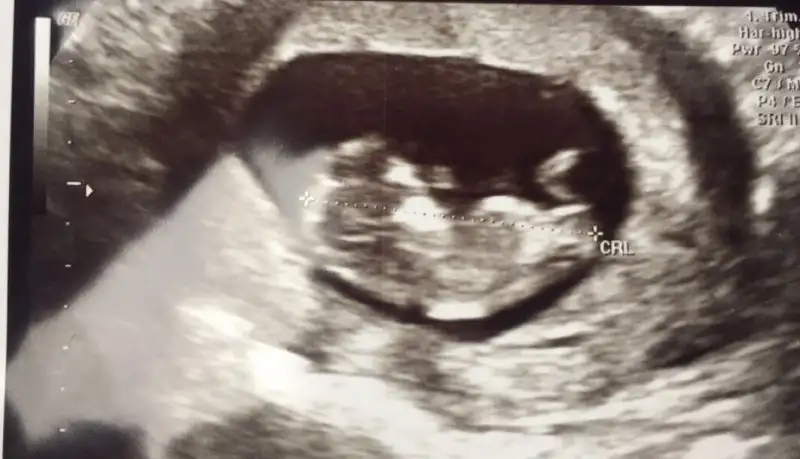

Bu da benim bebeğim teyzeler 10+4 te

Çok tatlı ya maşallah bizimkinin kafası 1 hafta önce soldaydı şimdi sağa geçmiş dr akvaryumun içinde şuan o diyo istediği yere geçer ama gerçekten nette de baktım cinsiyet tahmin etmek zor genelde hep erkek demişler sonradan kıza dönmüş çoğu dr yorumunda hayırlısı sağlıklı olsunlarda:dua:okadar kusuyorum mesela valla onun hiç umrunda değil keyfine bakıyor yan gelip yatmış :KK48: